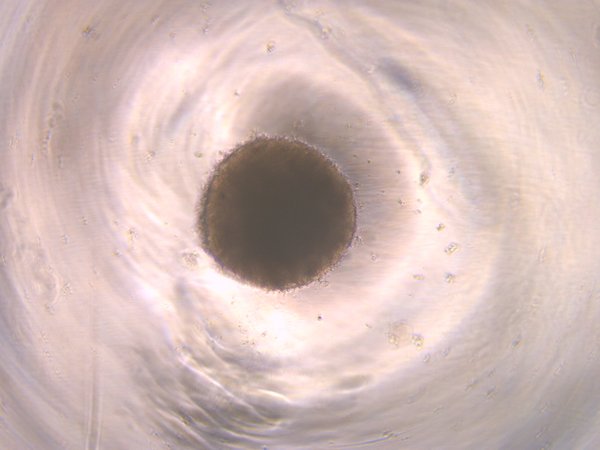

Disease Model A1A

A1A

TUBA1A mutation, Day 10